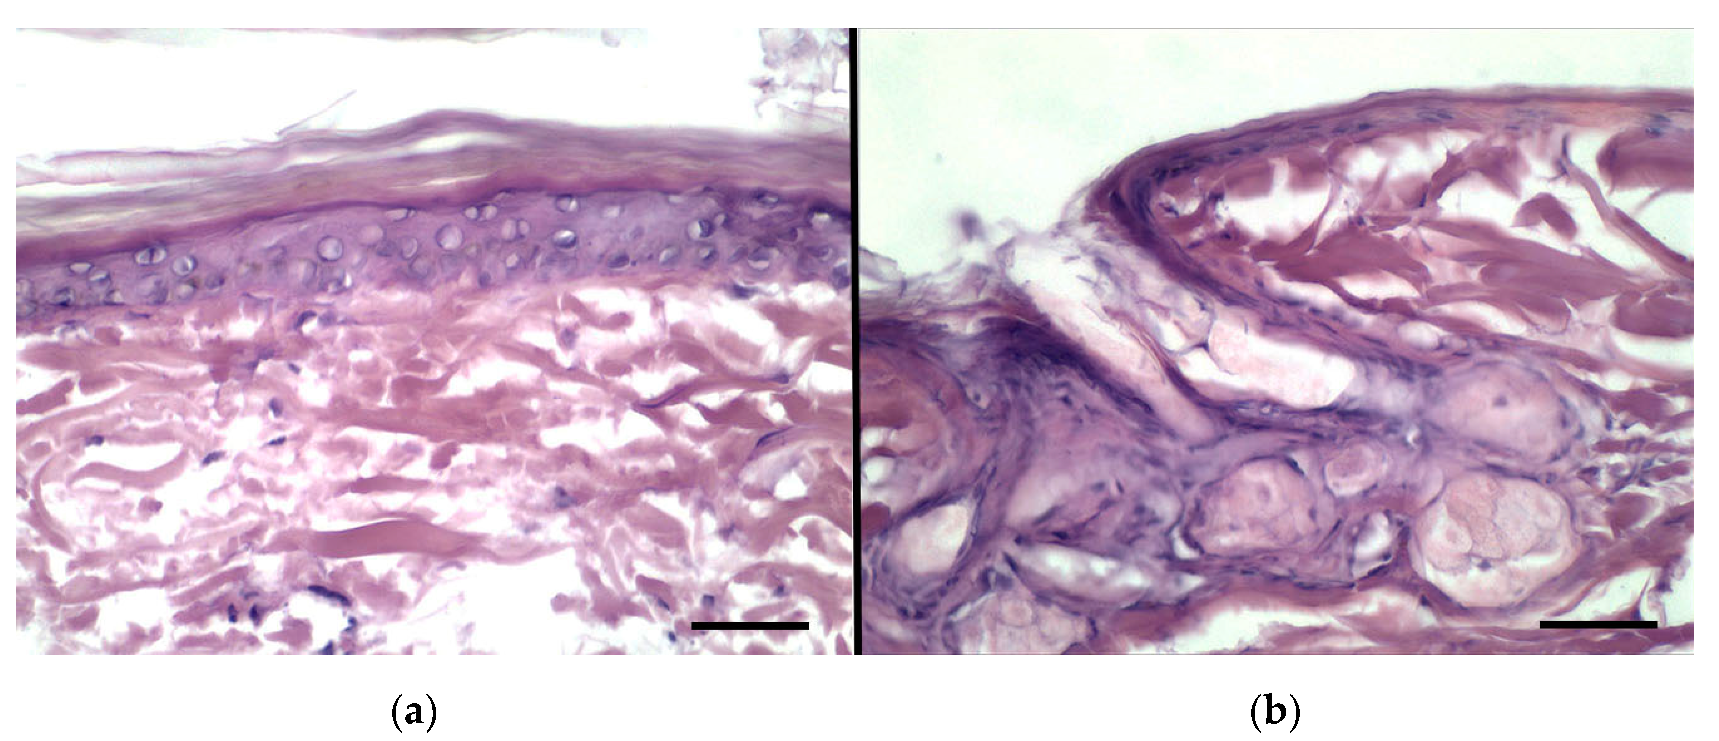

3.8. Histological Evaluation of Rabbit Ear Skin and Human Abdominal Skin

3.9. Percutaneous Penetration Studies and Subsequent Histological Analysis Using Rabbit Ear Skin